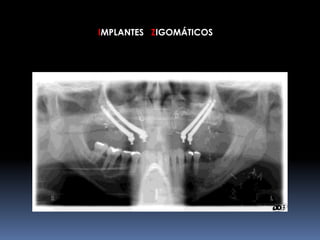

IMPLANTES ZIGOMÁTICOS     INDICAÇÕESMaxilar Edéntulo com Grande Reabsorção óssea		Pneumatização do Seio Maxilar	Status Pós-Maxilectomia	Fenda Lábio-Palatina

IMPLANTES ZIGOMÁTICOS